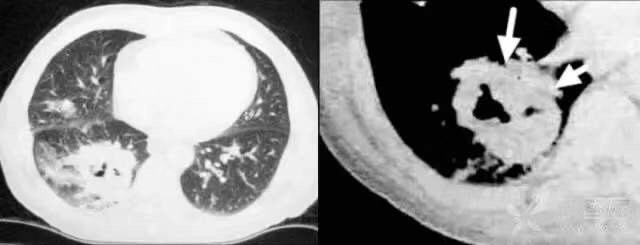

5.1. 1空洞

描述语及分型:薄壁空洞——厚度<3 mm;厚壁空洞——厚度>3 mm;无壁空洞——干酪性肺结核。

相关病变:肺脓肿、肺结核、肺癌等。如近肺门侧壁厚,可见壁结节,首先考虑肺癌,空洞形成。壁厚度均匀,内缘光整,腔内可见少量液体及低小气液平,多为良性空洞。

肺脓肿:右下肺可见一厚壁空洞,内可见液平,外缘模糊。

5. 1.2 癌性空洞:空洞壁厚薄不均,近肺门侧较厚,且可见壁结节凸向腔内。

5.1.3 干酪性肺结核:无壁空洞,多发空洞,呈所谓的「破抹布征」。